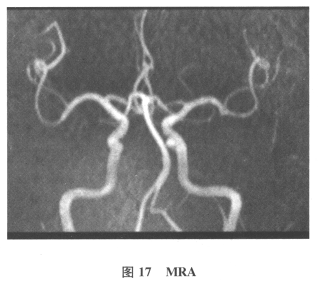

[单选题]患者男,61岁。因“发作性头晕2年,加重伴记忆力下降、走路不稳3月余”就诊。查体:BP140/70mmHg;意识清楚,构音障碍,近期记忆力及远期记忆力

[多选题]患者男,61岁。因“发作性头晕2年,加重伴记忆力下降、走路不稳3月余”就诊。查体:BP140/70mmHg;意识清楚,构音障碍,近期记忆力及远期记忆力